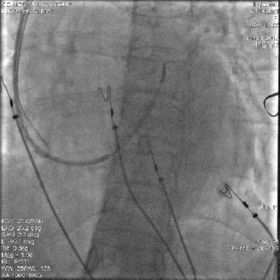

最终影像

AP

LAO

RAO